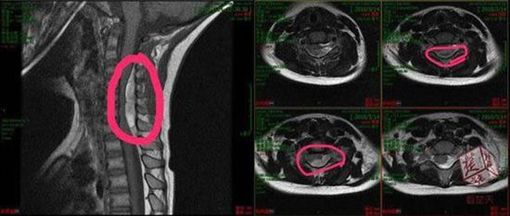

據陸媒報導,這名5歲男童幼稚園下課後便一直嚷嚷「脖子痛」,心疼的爺爺便帶孫子到附近的按摩店推拿,按摩完一小時,男童的身體便開始出現異狀,全身癱軟且手腳無力。祖父發現後,立即帶男童前往醫院就醫,沒想到醫生表示,男童的脊椎管內出血壓迫到神經,導致出現癱瘓症狀。

示意圖非當事人